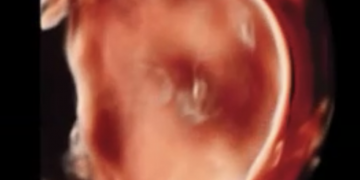

How To Do Luglio 2023: terminologia e classificazione MUSA

Cari soci, questo mese un nuovo video "How to do", dedicato alla terminologia e classificazione MUSA Grazie a Francesca Arezzo! Il video è accessibile ai soli soci SIEOG attraverso questo...